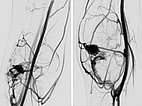

In der erneuten DSA 4 Monate nach der vorherigen Embolisation (links a.-p., rechts seitlich) zeigt sich ein frühes, umschriebenes Rezidiv. Gerade bei AVMs im Zusammenhang mit einem PTEN-Hamartom-Syndrom müssen die Patienten enge Nachsorgeintervalle einhalten da gerade diese AVMs eine hohe Rezidivneigung aufweisen.